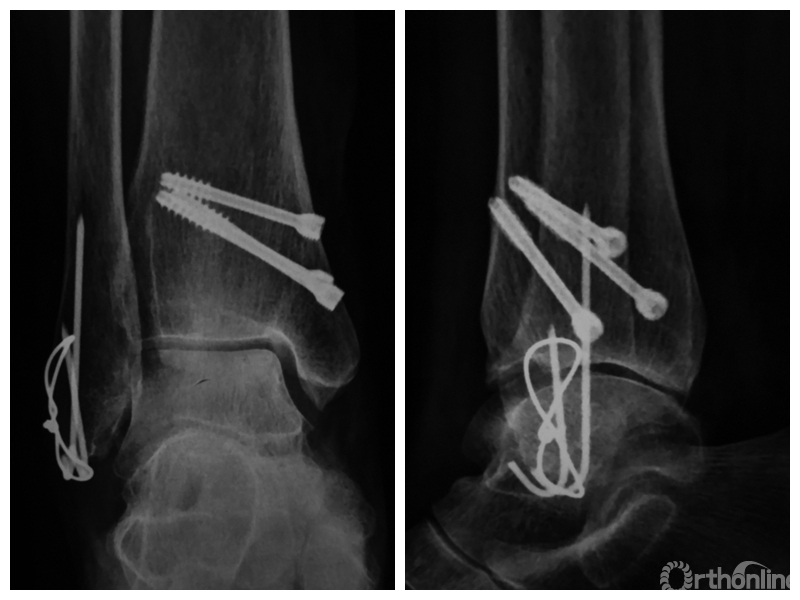

图1 支撑钢板固定组患者,女,63岁,右侧旋后-内收型II度踝关节骨折 a. 术前正侧位X线片;b. 术前CT;c. 术后2周正侧位X线片;d. 术后2年正侧位X线片

图1d 术后2年正侧位X线片

两组患者均获随访,支撑钢板固定组随访时间46~91,平均64.5个月;螺钉固定组随访时间44~86,平均59.5个月。支撑钢板固定组患者术后完全负重时间为(11.5±1.6)周,较螺钉固定组的(12.6±2.3)周显著缩短,比较差异有统计学意义(t=2.05,P=0.04)。X线片复查示,支撑钢板组均获解剖复位,均达愈合;螺钉固定组有20例获解剖复位,2例畸形愈合,1例不愈合,支撑钢板组骨折愈合时间为(11.5±1.6)周,螺钉固定组为(12.0±1.7)周,比较差异无统计学意义(t=1.06,P=0.30)。见图1、2。支撑钢板固定组3例(10%)、螺钉固定组4例(17.4%)发生创伤性关节炎,均采取保守治疗;两组比较差异无统计学意义(P=0.45)。

末次随访时,支撑钢板固定组AOFAS评分为(83.5±9.3)分,其中优8例、良17例、可5例,优良率为83.3%;螺钉固定组AOFAS评分为(76.7±21.2)分,其中优5例、良13例、可2例,差3例,优良率为78.3%。两组AOFAS评分及其优良率比较,差异均无统计学意义(t=1.57,P=0.12;χ2=0.22,P=0.64)。支撑钢板固定组VAS评分为(1.7±1.3)分,螺钉固定组为(2.6±2.1)分,组间比较差异无统计学意义(t=1.92,P=0.06)。随访期间,支撑钢板固定组无手术失败;螺钉固定组3例需行翻修手术,其中1例骨折不愈合合并内固定断裂,2例骨折畸形愈合,手术失败率为13%;但组间比较差异无统计学意义(P=0.08)。